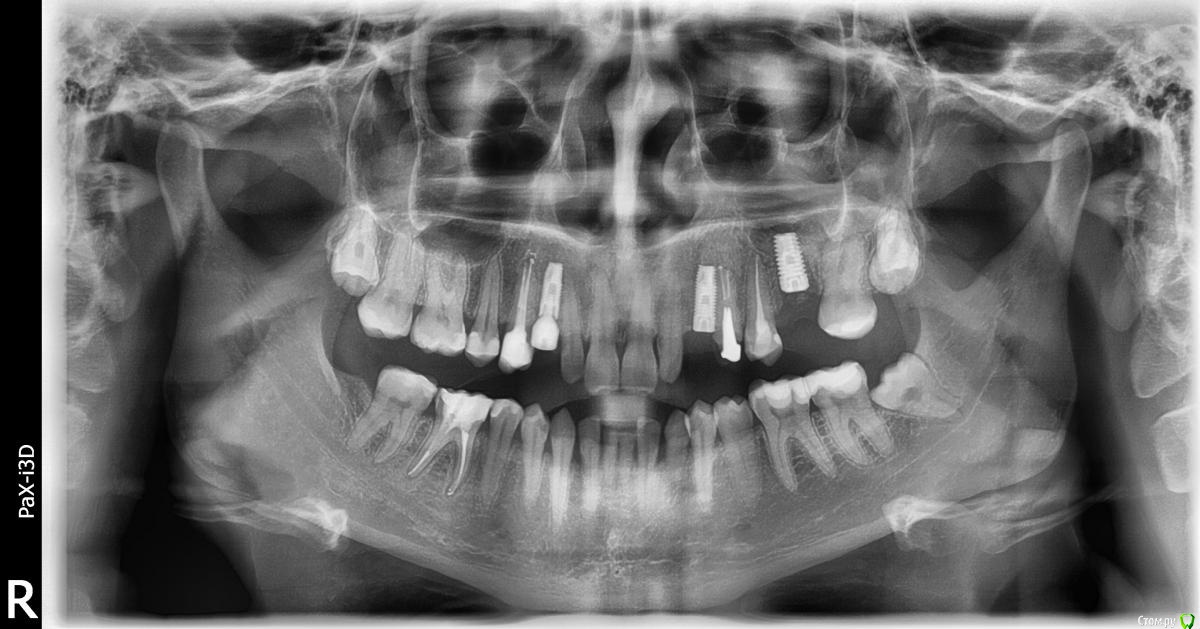

fifa888.dexo Опубликовано 13 июля, 2015 Поделиться Опубликовано 13 июля, 2015 Здравствуйте. На верхней челюсти четвертый зуб слева. Перелечили каналы, поставили вкладку из циркония и поставили временную коронку так как готовилась к имплантации.Сейчас сделала снимок и увидела пустое расстояние между каналами и вкладкой,подскажите что это такое,так должно быть?К своему ортопеду записана только на 19 августа,он у нас в городе считается очень хорошим и к нему большая запись,так делал все аккуратно мне все очень понравилось.,но вкладка смущает.... Ссылка на комментарий

anvladd Опубликовано 13 июля, 2015 Поделиться Опубликовано 13 июля, 2015 Не переживайте так бывает, скорее всего материал нерентгеноконтрастный на который фиксировали вкладку. 4 Ссылка на комментарий